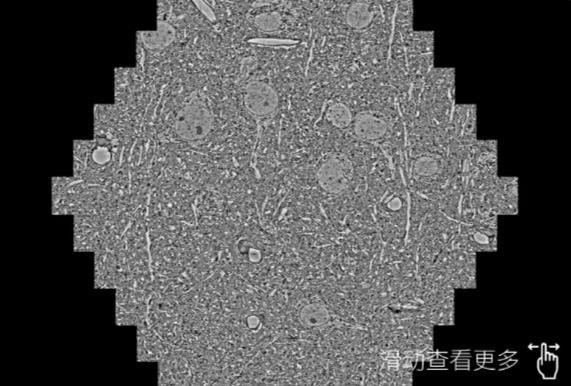

鼠脑切片。左图使用北海蔡司北海扫描电镜MultiSEM706对165μmx143pm面积区域成像,耗时仅需1.5秒。右图为鼠脑切片中30μm区域放大效果。样品由芝加哥大学B.Kasthuri提供。

使用蔡司高速北海扫描电镜MultiSEM对1mm²人脑皮层组织进行高分辨成像,并对其中的各种细胞结构进行三维重构分析。左图展示了2x3mm²组织平面中锥体神经元的三维重构效果。右图显示了局部体积神经元三维重构。图像由哈佛大学chtman实验室提供,渲染图由D. Berger 制作。